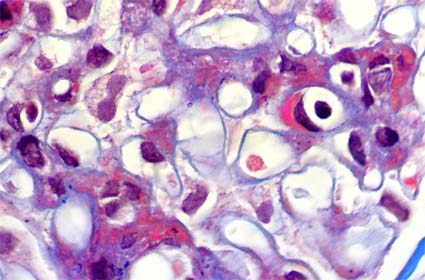

Con diagnóstico de LES se hace

biopsia renal para determinar compromiso por la enfermedad. Observe

las imágenes.

Figura 3.

PAS, X400.